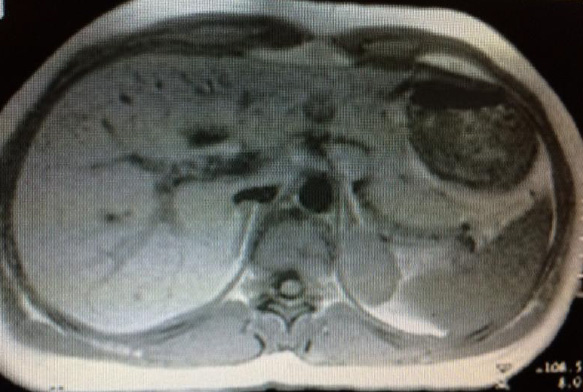

Интраренальная лоханка: рентгеновские снимки и примеры

Раздел: Фотоэссе